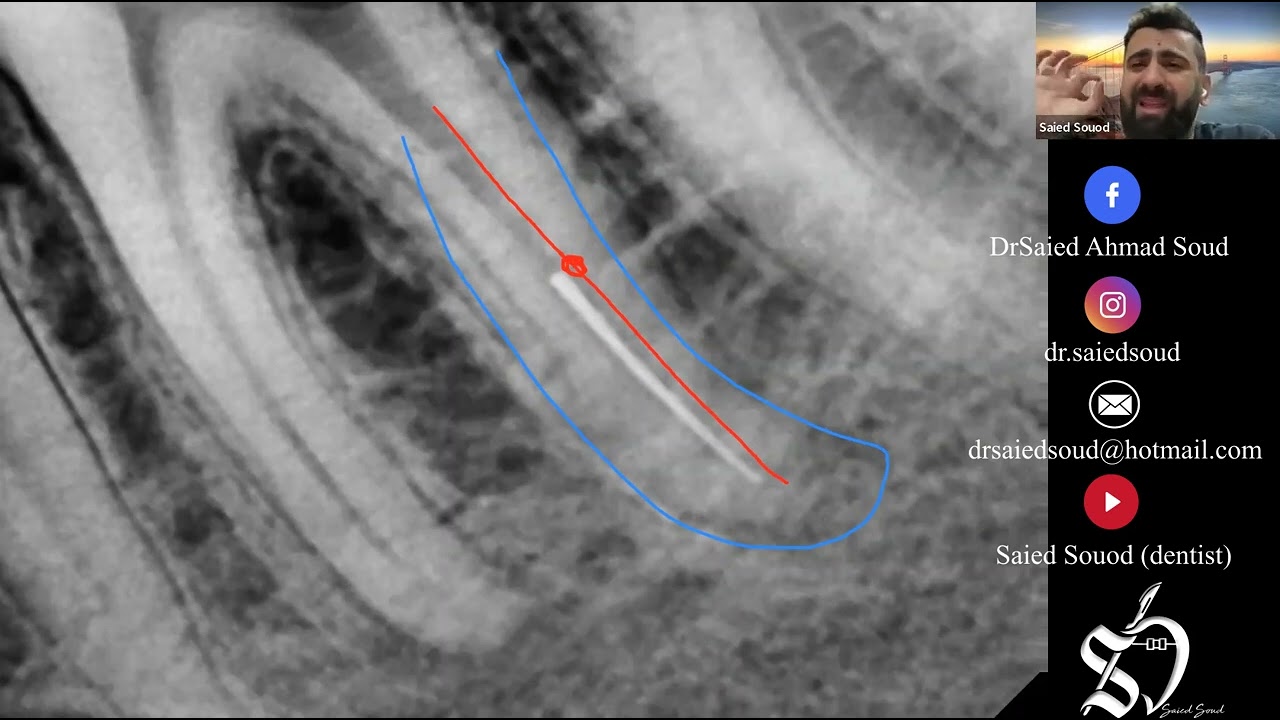

Endodontics is nowadays becoming more and more user-friendly with modern rotary or reciprocating files; however despite introducing new products, protocols are still prone to failure. One of the most common problems in endodontics is the formation of a ledge. This deviation from the original canal can be fatal for a tooth.

Managing a ledge can be a real challenge. Ledges lead to mistreatment and poor outcome. Main causes for ledges are improper instrumentation of a canal, pushing instruments or failing to use instruments in sequential order. When scouting a canal, one has to be very tactile and try not to push instruments. Sometimes its also connected with improper access.

All NiTi instruments have two features, one bad and one good. Both are called "shape memory". On one hand it's good that files are flexible and adopt to the curvature of a canal. On the other hand, the problem occurs when we stop on the curvature with a rotating file. It’s proceeding while cutting on the outer part of a curvature. Time needed to develop a ledge depends on the construction of a file (more agressive file means faster ledge). It happens because the file wants to come back to its programmed shape (straight). Ledges can also be done with too rigid, fast or aggressive hand file introduction in the canals.

Knowing that issue can help us prevent from doing ledges, but sometimes it happens. So what to do in that situation. In order to pass a ledge, one have to pre-bend a file in a special way. Not as most of us do it. One has to use the advantages of a canal anatomy. What is good is that it's impossible to do a ledge on the inner curvature and this would help us pass a ledge more easily and more predictably. Ledges always occur on the outer curvature.

Mostly inner curvatures don't have any obstructions. Knowing that, we can use it to guide a steel hand file to pass a ledge very efficiently. First, what one has to do is to pre-bend a file in a fishing hook style. Then next step will be to advance it in the canal in a way that a tip of a file always goes toward the inner curvature.

A ledge is a deviation from the original pathway of the canal created by the clinician during the instrumentation. Two factor are needed to create a ledge: the first is the presence of a curved canal, the second is an inappropriate approach during the instrumentation by the clinician.

Once the ledge is created, if the clinician continues to force the manual/rotary file, a perforation could be created. The ledge impedes access of instruments to the apex, thus canal blockage is caused by packing dentin chips and/or tissue debris: as a result, the portion of canal located apically to the ledge it is not shaped, cleaned and filled, and this is the reason why it is well recognized by the scientific community that there is a strong relationship between ledge creation and negative outcome of the therapy. According to the Literature we well know that working through contracted access cavities, forcing file/rotary file in curved canals and an improper WL registration are all factors that could lead to a ledge formation. Knowing the etiology of the ledge is really helpful to prevent its creation and during the treatment of curved canals helps us paying attention to all these factors.

The ledge is always in the external wall of a curved canal

It’s really important to know how deep is the ledge and the WL in order to choose the best operative strategy to complete properly the endodontic treatment

Prebendig a manual file is still a very important stage to manage a ledge

Martensitic rotary files at body temperature are very helpful to quickly and safely manage a ledge